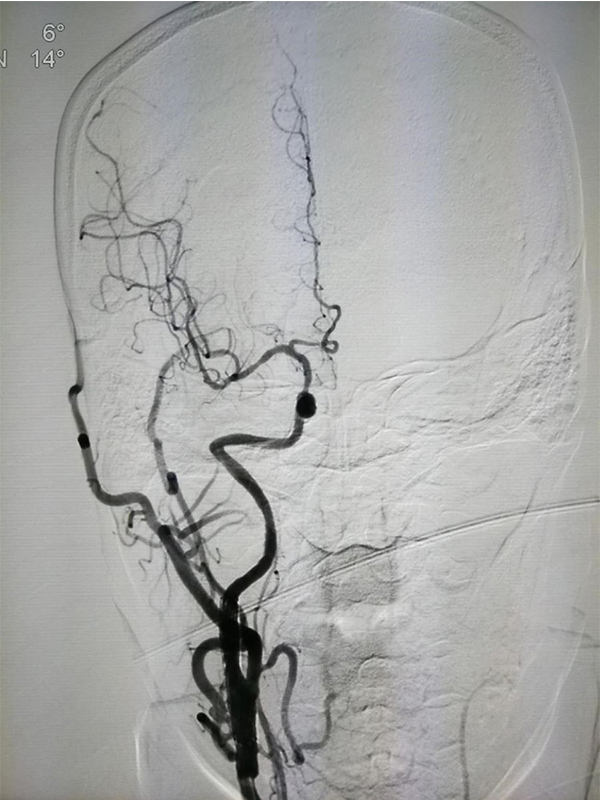

MRA CTA (CT ) DSA <50 %) MRA 50 % CTA 80% DSA 99 % ( ) CTA DSA

CTA 100 % 63 %(95 % 25 %-88 %) 70 % 100 %

NASCET 1 % MRA CTA